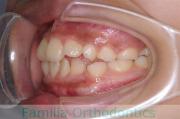

No.19V-044

- 上顎前突

- 13歳

- 女性

- 上:

- 44

- 下:

- 8558

- 主な使用装置:

- FEA

- 治療にかかった費用:

- 85万円

出っ歯を治したいということで小学生の時に来院されました。中学生になるまで経過観察をして、診断、上下左右から小臼歯を抜歯してマルチブラケット法にて治療を行いました。2年強、30回程度の通院が必要でした。

口元の突出感も大きく改善しています。

右側

正面

左側

上下とも前歯の叢生(でこぼこ、凹凸、ガタガタ)がありましたので、保定をしっかりやらないと後戻りのリスクが出てきます。